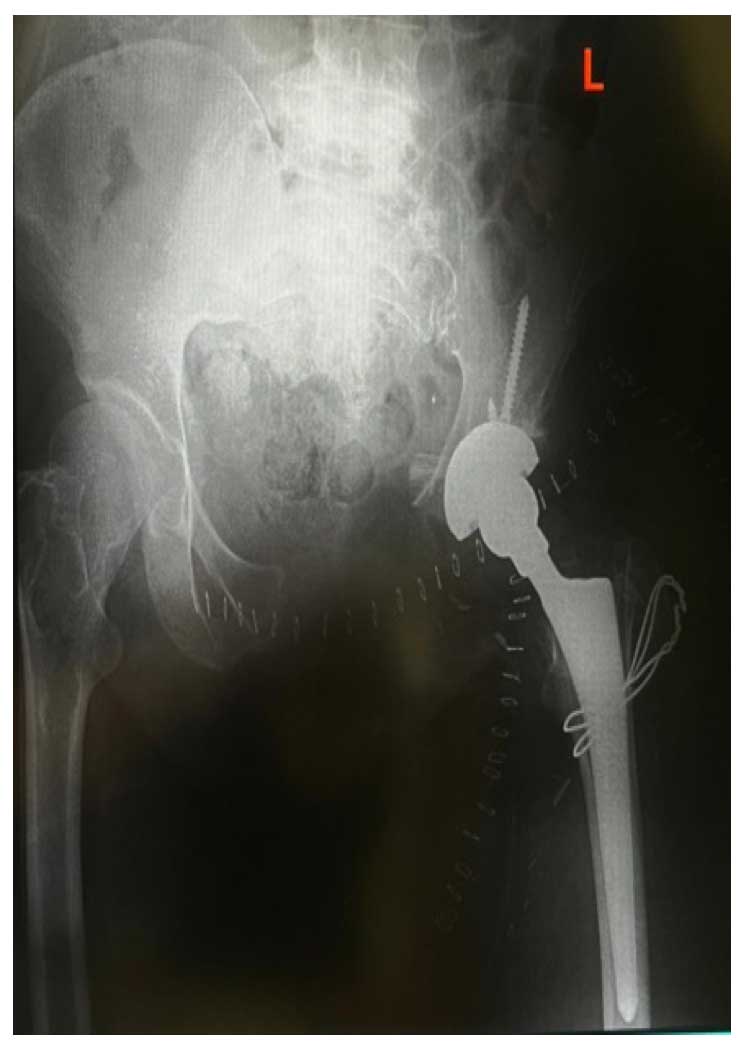

Hastaya internal hemipelvektomi (Tip III + kısmi Tip II) uygulandı. Rezeksiyon sonrası defekt total kalça protezi ile rekonstrükte edildi.

Ameliyat Sonrası: Röntgende rezeksiyon sonrası total kalça uygulanımı görülmekte.